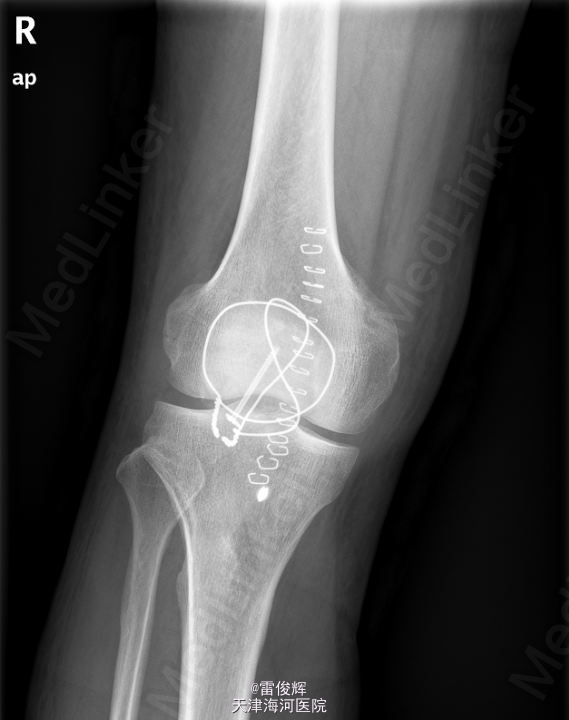

初步诊断: 右髌骨骨折 患者入院后完善检查,排除禁忌,全麻下行右髌骨骨折切开复位内固定+髌韧带修补术。

术后予抗炎止痛护胃补液等对症支持治疗.创口清洁,干燥,无感染征象,肢端活动感觉可,术后X片提示骨折复位固定满意.